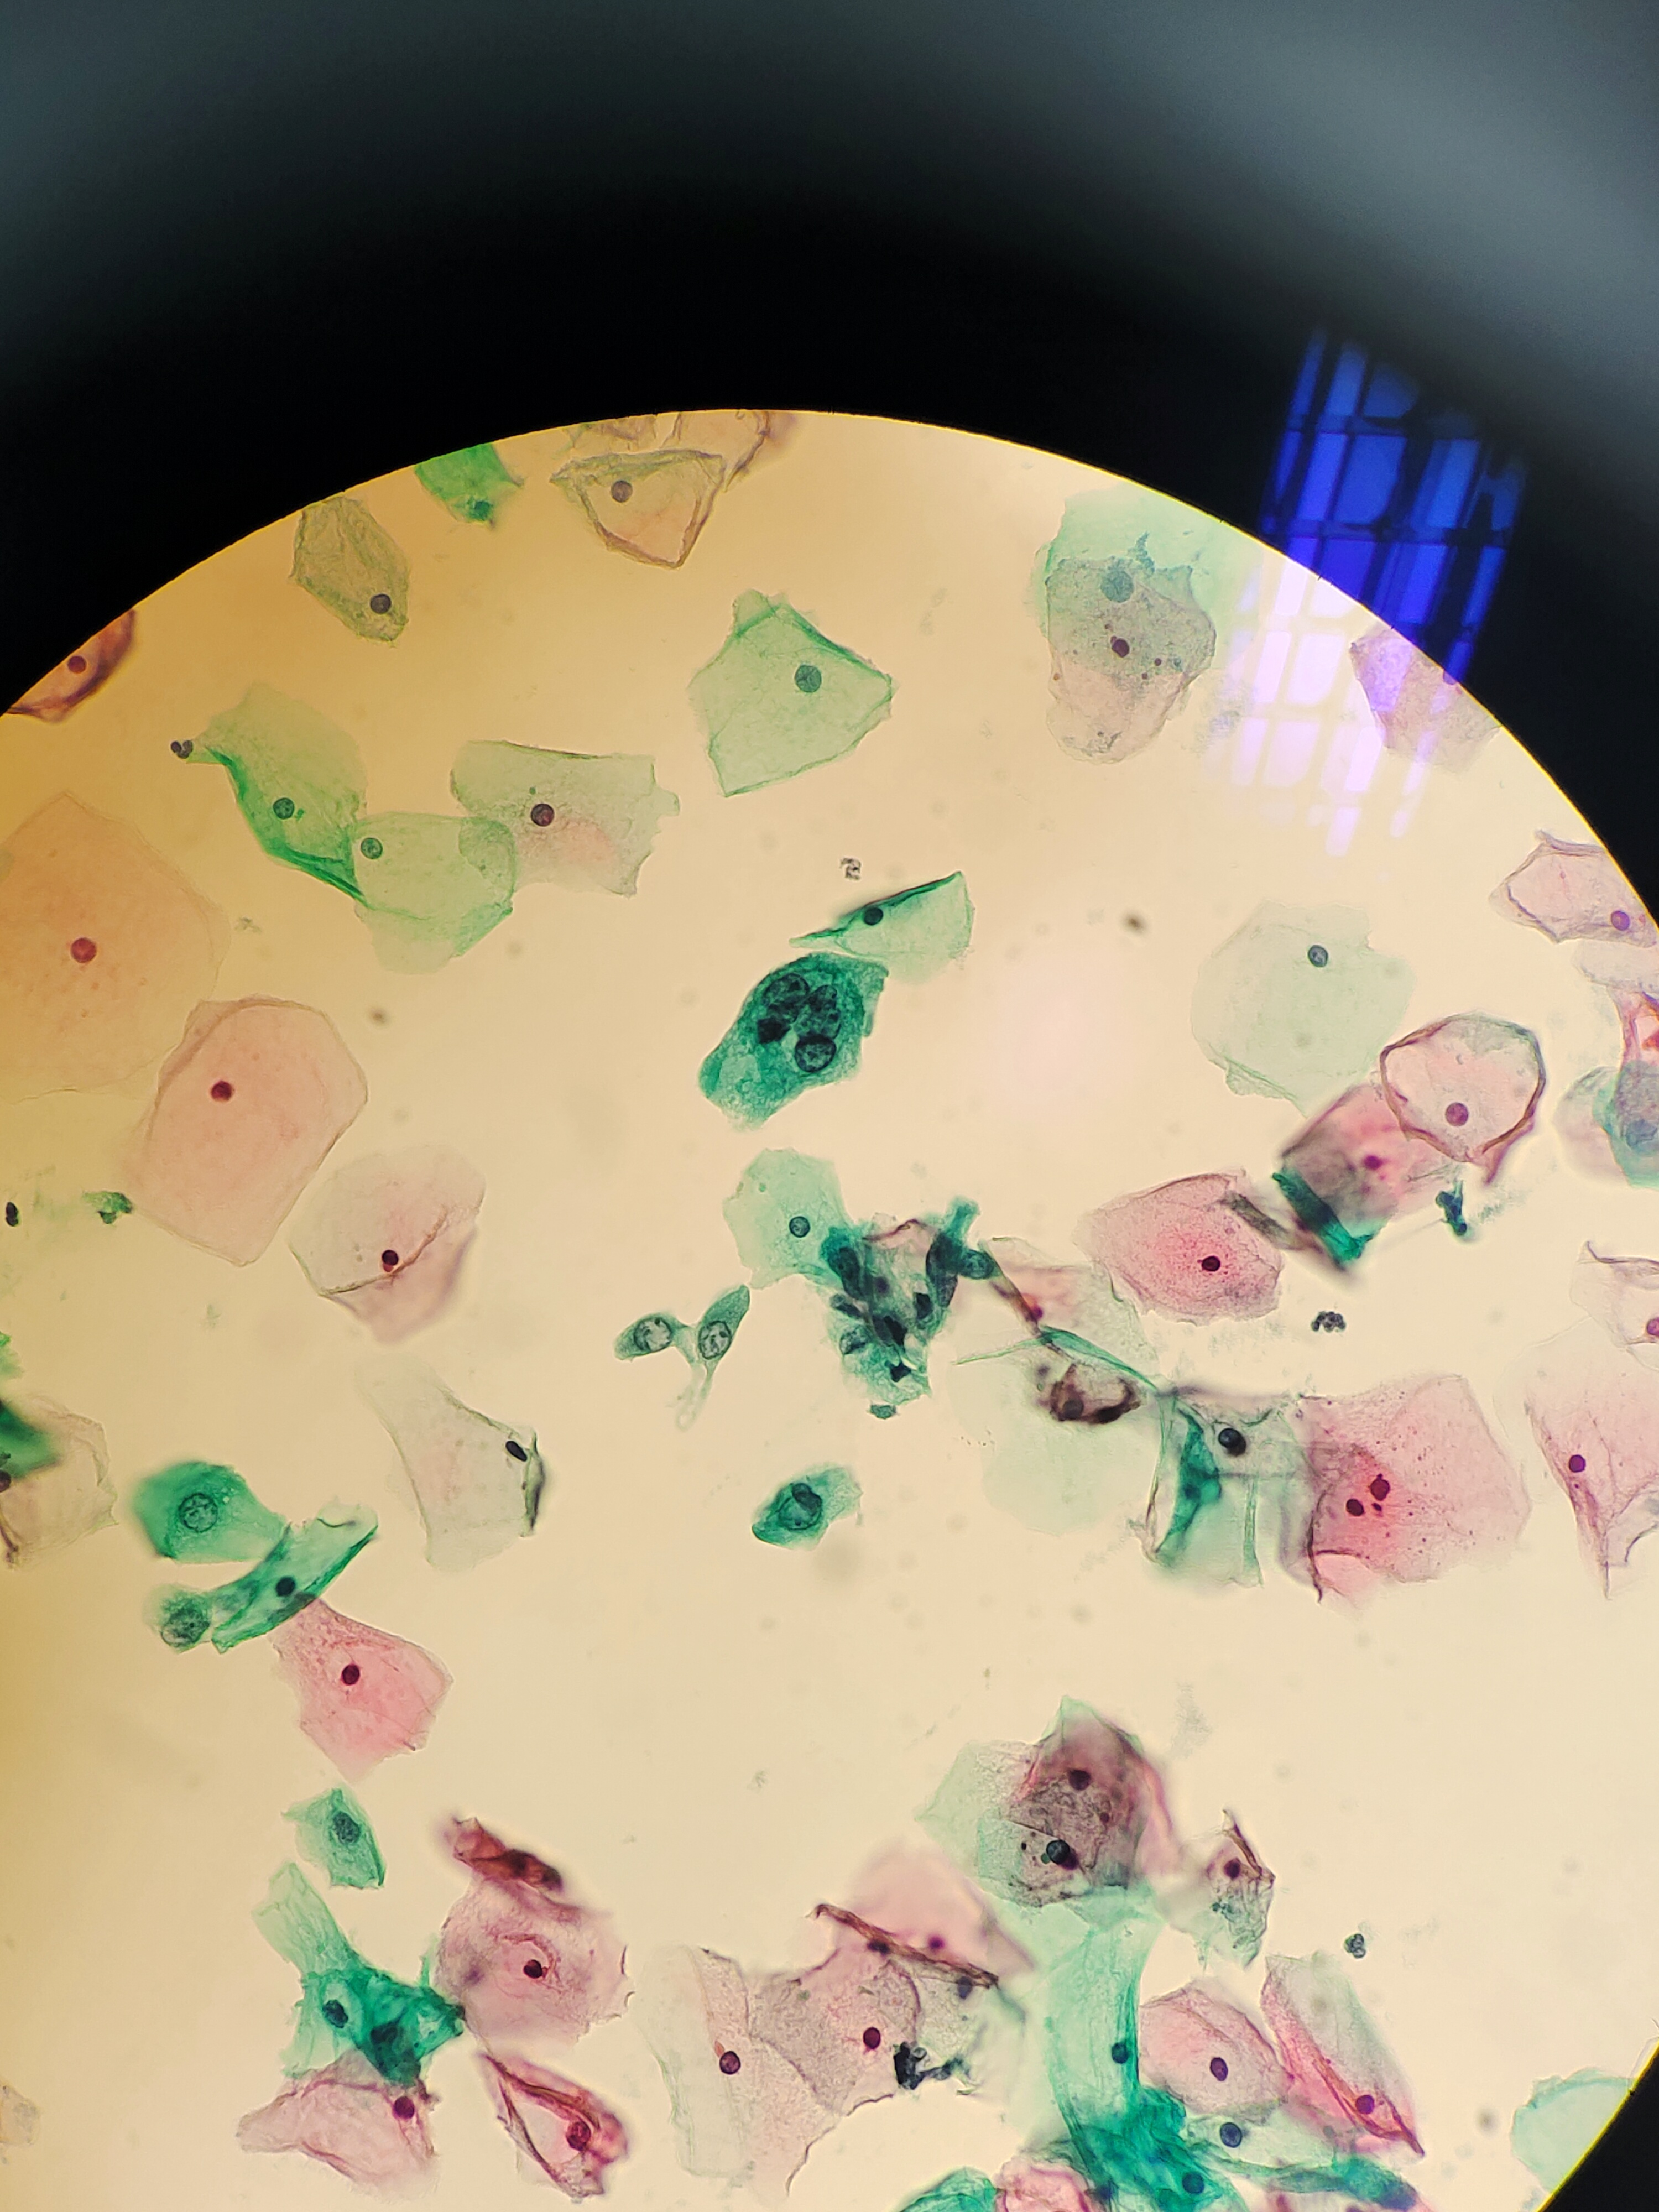

自觉外阴酸胀不适,分泌物无异常,宫颈多发囊肿,HPV未查。老师们,有些核大细胞,就最后一张深染,怎么报呢?

宫颈

液基

巴氏

ASCUS